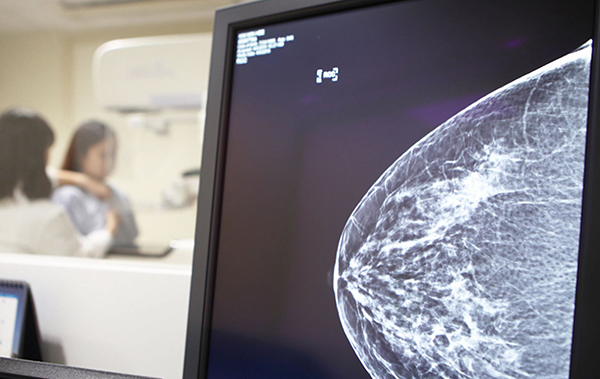

[문화투데이 구재숙 기자] 우리나라 인삼으로 만든 흑삼이 전 세계 여성에게 가장 흔한 악성 종양인 유방암에 큰 항암효과를 보이는 것으로 나타났다.

이승태 강원대학교 동물생명응용과학과 교수팀은 흑삼이 사람의 유방암 세포 증식과 성장 억제에 미치는 영향을 조사해 이 같은 사실을 확인했다고 밝혔다.